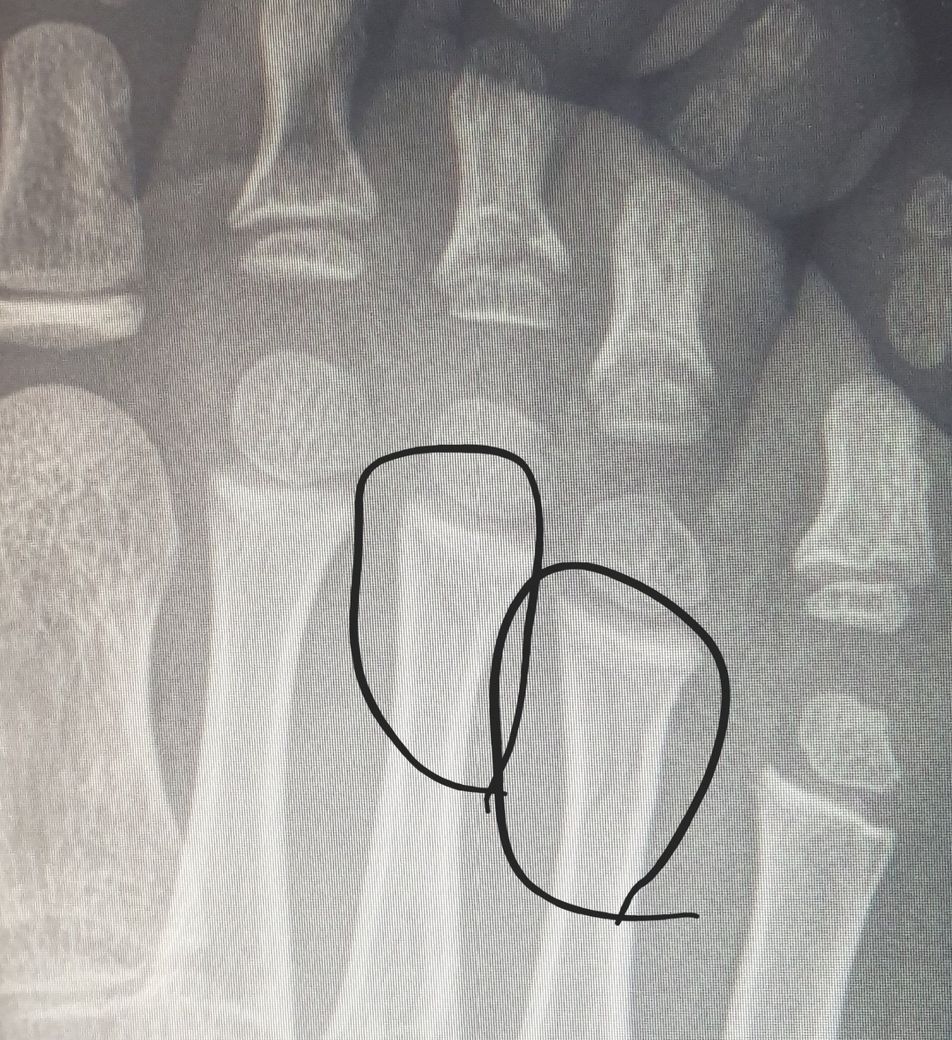

5살 둘째가 부페 놀이방에서 놀다 발등2곳이 미세골절이 됫어요ㅜㅜ

애가 통깁스 하니..안쓰럽네여ㅜㅜㅜ후..

어린 아이가 깁스를 한 사진을 보니 마음이 아프네요.